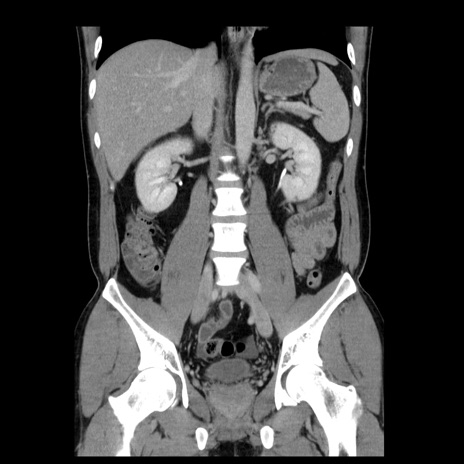

症例4(冠状断像)

【症例】30歳代男性

【主訴】腹痛、嘔吐

【現病歴】昨晩から突然の腹痛あり、その後嘔吐、軟便も出現。腹痛が改善しないため救急搬送となる。2日前にしめ鯖の食事歴あり。

【身体所見】意識清明、苦悶様、BP 135/90mmHg、BT 35.7℃、腹部:平坦、やや硬、心窩部〜臍部に自発痛、圧痛あり、筋性防御+、反跳痛-

【データ】WBC 8100、CRP 0.57